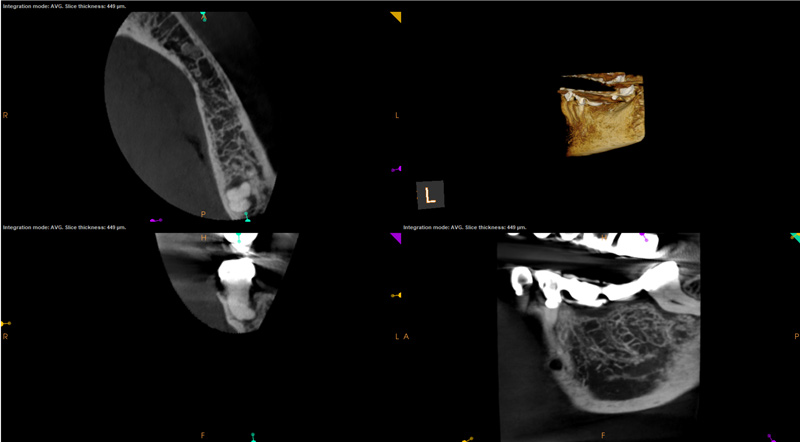

In the first case study, a young female patient was told she had a tooth (tooth No. 2, Figure 3) that should be extracted due to extensive bone loss. Using CBCT, the clinician was able to identify a large lateral canal within the palatal root. Despite the bone loss, the patient was eager to save her tooth. He offered to treat the tooth with the broad-spectrum acoustic technology. As shown in Figure 4, the preparation space was much smaller, which he was able to obturate efficiently. In addition, the small pinpoint of sealer in the middle of the palatal root indicated that the palatal lateral canal had been addressed (Figure 5). In the clinician's opinion, this area was likely the primary source of much of the bone loss.

Figure 6 through Figure 8 demonstrate that, 5 months after the procedure, complete healing had occurred, notably on the distal, where the probing had resolved to 2 mm. The patient then had a crown placed by her general dentist. Given her positive experience with the technology, she was eager to return as needed for continued follow-up.

Fig 5. Case 1: CBCT showed a large lateral canal within the palatal root (Fig 3). There was a small preparation space, which was efficiently obturated (Fig 4). A small pinpoint of sealer in the middle of the palatal root indicated that the palatal lateral canal had been addressed (Fig 5). After 5 months, CBCT demonstrated complete healing (Fig 6), notably on the distal, where probing had resolved to 2 mm. Radiographic images were taken immediately postoperatively (Fig 7) and 5 months postoperatively (Fig 8).

Figure 5

Fig 6. Case 1: CBCT showed a large lateral canal within the palatal root (Fig 3). There was a small preparation space, which was efficiently obturated (Fig 4). A small pinpoint of sealer in the middle of the palatal root indicated that the palatal lateral canal had been addressed (Fig 5). After 5 months, CBCT demonstrated complete healing (Fig 6), notably on the distal, where probing had resolved to 2 mm. Radiographic images were taken immediately postoperatively (Fig 7) and 5 months postoperatively (Fig 8).

Figure 6

Fig 7. Case 1: CBCT showed a large lateral canal within the palatal root (Fig 3). There was a small preparation space, which was efficiently obturated (Fig 4). A small pinpoint of sealer in the middle of the palatal root indicated that the palatal lateral canal had been addressed (Fig 5). After 5 months, CBCT demonstrated complete healing (Fig 6), notably on the distal, where probing had resolved to 2 mm. Radiographic images were taken immediately postoperatively (Fig 7) and 5 months postoperatively (Fig 8).

Figure 7

Fig 8. Case 1: CBCT showed a large lateral canal within the palatal root (Fig 3). There was a small preparation space, which was efficiently obturated (Fig 4). A small pinpoint of sealer in the middle of the palatal root indicated that the palatal lateral canal had been addressed (Fig 5). After 5 months, CBCT demonstrated complete healing (Fig 6), notably on the distal, where probing had resolved to 2 mm. Radiographic images were taken immediately postoperatively (Fig 7) and 5 months postoperatively (Fig 8).

Figure 8